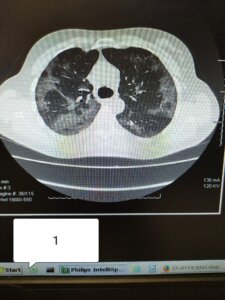

Galmozzi ha poi pubblicato 3 immagini di TC:

1) soggetto di 52 anni NON VACCINATO, senza malattie in anamnesi

“Se in 1) e 2) il carico di malattia polmonare è elevato in 1 (circa 60%) e discreto in 2) (circa 35%). Nel soggetto 3) (fragile e con malattie importanti in anamnesi), la malattia non c’è. I primi due ricoverati e con ossigeno, il terzo a casa sua”.